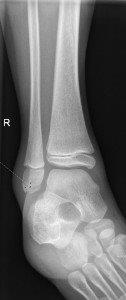

Avulsion fracture of distal fibula

- No formal follow up required.

Salter Harris I fracture of fibula

Undisplaced Salter Harris II fracture of fibula

- Follow up GP 7-10 days for repeat X-ray.

- If displaced, not suitable for CAM Boot.

Undisplaced epiphyseal fracture of distal fibula